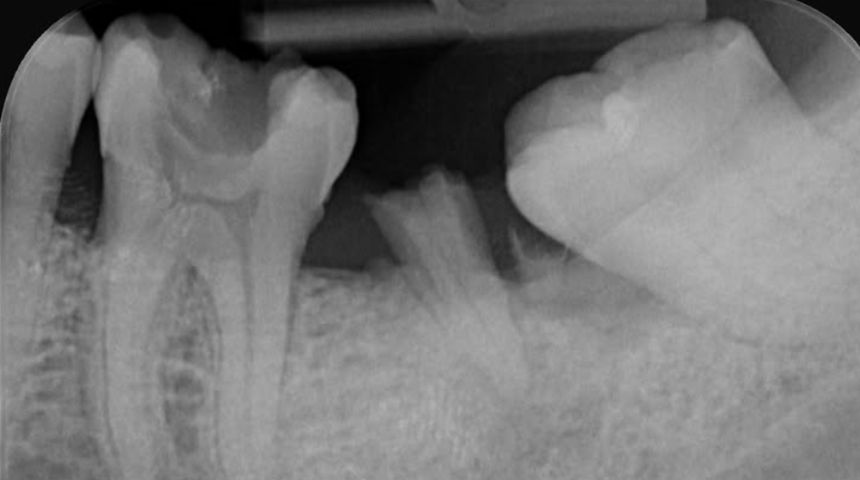

Take a look at some of our recent cases below!